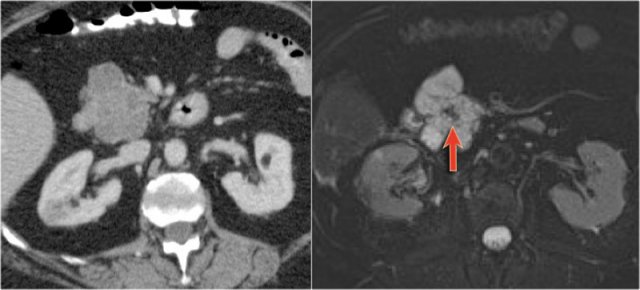

Scroll through the images of a large main duct and branch-duct IPMN.

There is obstruction of the common bile duct with dilatation of the intrahepatic bile ducts (blue arrows).

Notice the extremely widened main pancreatic duct (red arrow).

Normal T2WI and heavily T2WI with fatsat of a large main duct IPMN with extremely dilated pancreatic duct.

This patient presented with pancreatitis.

The MRCP shows both a main-duct aswell as a branch-duct IPMN (arrow).